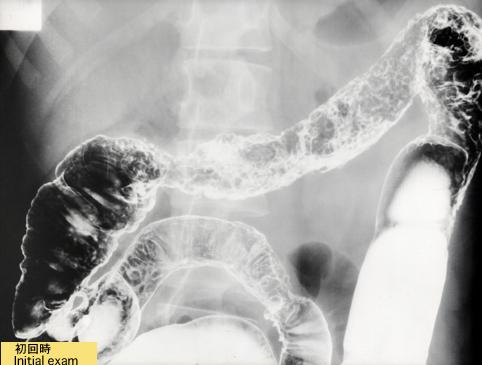

크론병으로 보여진 염증성 용종증(case 2)

종양양 병변/염증성 용종증

대장/2구역 이상의 대장에 걸치는 것

X-P

1~9